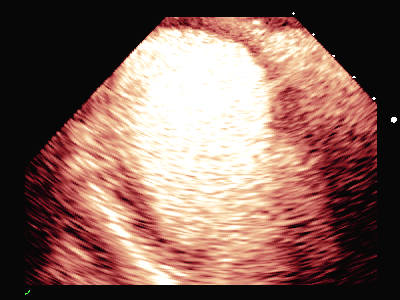

图(3)

图(4)

图(5)

运动平板试验阳性:运动中第4阶段窦性心率157次/分时,出现短阵室性心动过速。前间壁ST段抬高,下壁及前侧壁ST段压低,休息后恢复。